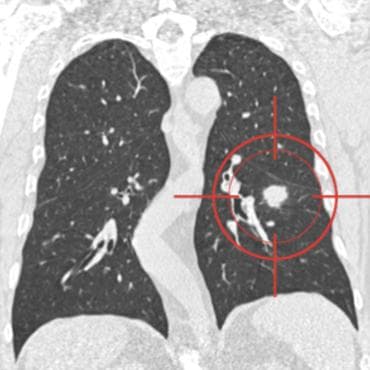

The LUNA challenges provide datasets for automatic nodule detection algorithms using the largest publicly available reference database of chest CT scans, the LIDC-IDRI data set. In LUNA16, participants develop their algorithm and upload their predictions on 888 CT scans in one of the two tracks: 1) the complete nodule detection track where a complete CAD system should be developed, or 2) the false positive reduction track where a provided set of nodule candidates should be classified.